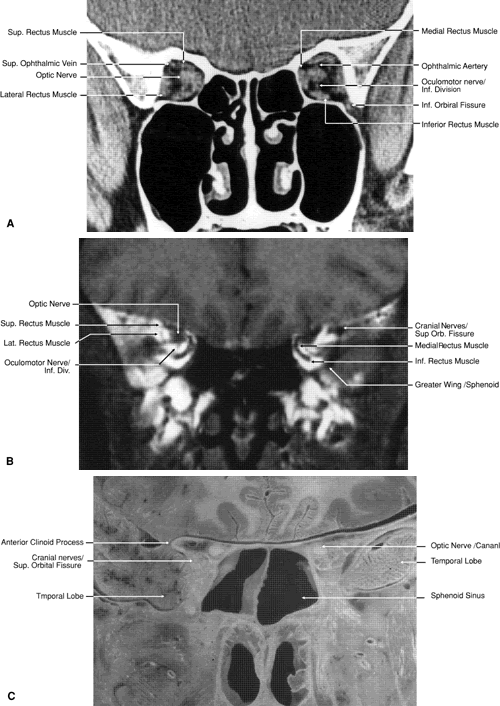

Fig. 17. Coronal images through anterior orbit. A. Computed tomography scan. B. T1-weighted magnetic resonance imaging.

Fig. 18. Coronal images through midglobe. A. Computed tomography scan. B. T1-weighted magnetic resonance imaging.

Fig. 19. Coronal images through midorbit posterior to the globe. A. Computed tomography scan.B. T1-weighted magnetic resonance imaging.

Fig. 20. Coronal images through orbital apex. A. Computed tomography scan. B. T1-weighted magnetic resonance imaging. C. Anatomic section of a cadaver head at the level of the orbital apex.